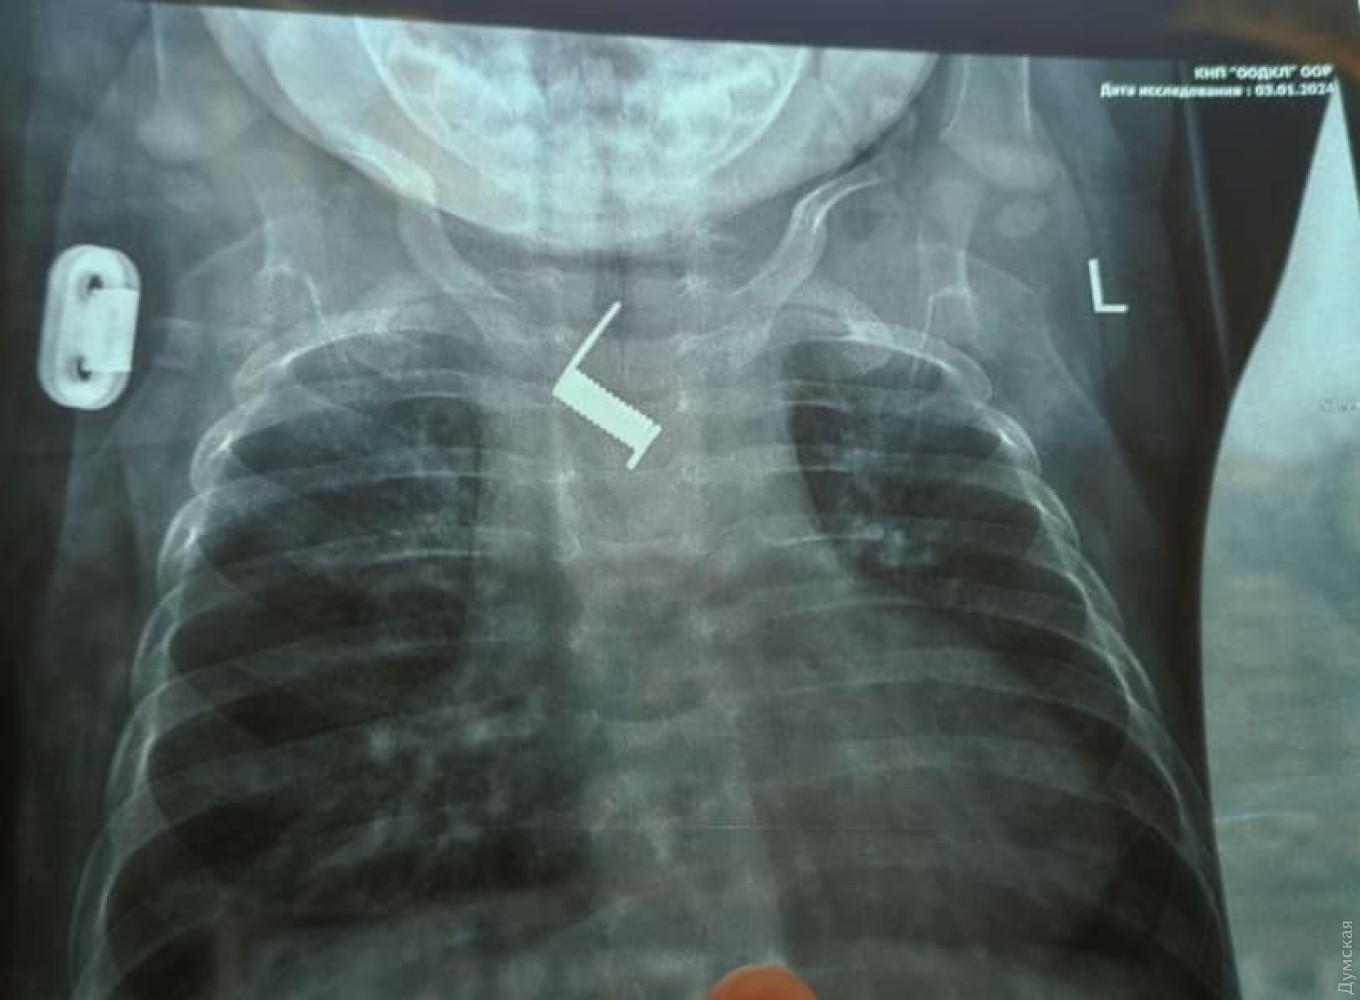

Хірурги Одеської обласної дитячої клінічної лікарні витягли пружинку від заколки для волосся зі стравоходу шестимісячної дитини.

В установі зазначили, що сторонню річ вдалося виявити під час ренгтену. До цього дитину в районній лікарні два тижні безуспішно лікували від бронхіту та пневмонії.

За цей час пружинка практично вросла в стінку стравоходу. Предмет вдалося витягти за допомогою ендоскопії, що убезпечило дитину від тяжкого хірургічного втручання.